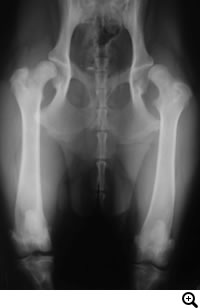

レッグペルテス / 大腿骨頭無菌性壊死症

レッグペルテス / 大腿骨頭無菌性壊死症とは

成長期に大腿骨頭への血液供給が不足することで大腿骨頭壊死が生じ、関節軟骨が消失することで痛みが引き起こされます。

好発犬種

ヨークシャテリア・トイプードル・チワワ等の小型犬種に好発する疾患です。膝蓋骨内方脱臼の好発犬種と類似しており、併発していることもよくあります。多くは5ヶ月〜11ヶ月齢で症状がでます。

診断

レントゲン検査

後肢の跛行が成長期に起こる場合には要注意です。早期発見早期治療が重要です。

• THR(Total Hip Replacement)/ 股関節全置換術

Micro THR(Micro Total Hip Replacement)/ 小型犬・猫用股関節全置換術

• FHO(Femoral Head Osteotomy)/ 骨頭切除術

全股関節置換術は股関節形成不全やその他の股関節の異常(レッグペルテス、骨頭骨折等)に対して行われる根治的治療法で、機能の回復に関しては現在のところ最もすぐれた治療法です。機能しない、あるいは痛みを持つ股関節をチタンの人工関節に取り替える方法です。6カ月齢からあらゆる年齢で可能な手術です。

大腿骨頭を切除することで、寛骨臼と軟骨が損傷した大腿骨頭の直接的な接触をなくし痛みを取り除く方法です。何らかの原因でその他THR・DPO・TPOの手術ができない場合、保存的療法に反応しない場合、救済的な手術としておこないます。骨頭を切除した関節周囲に線維性偽関節が形成されるまで、不安定になるため、患肢を着地し負重するようになるまである程度の期間を要します。歩様が改善されるまで、リハビリテーションを行いながらサポートをいたします。